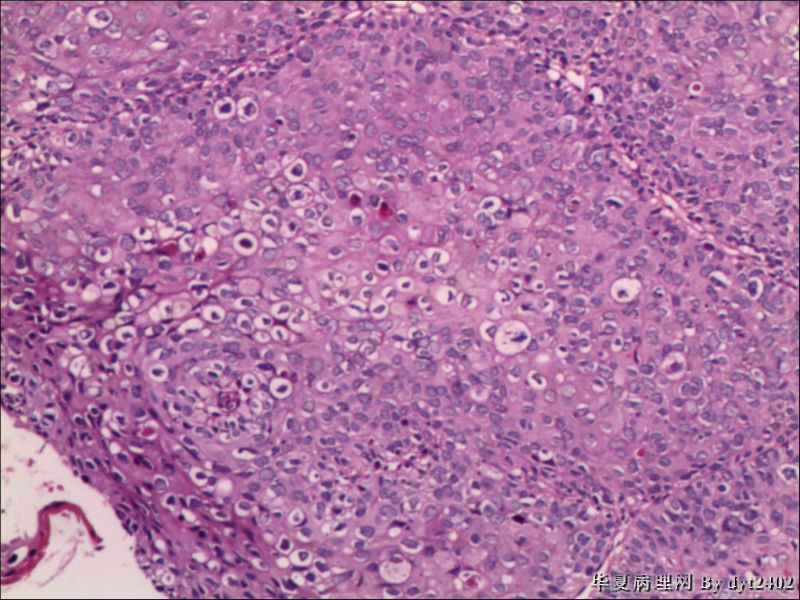

四点中三点是CIN iii,另一点怀疑有更重病变

这个病人是44岁,去年11月底阴道脱落细胞、TCT均见细胞异常,建议活检,病人犹豫,接着单位组织到外院体检时做阴道镜正常,后霉菌感染,此时宫颈未涂醋肉眼看还光滑,直至今年3月来做活检,事前做白带检查又见异常细胞,宫颈未涂醋见后上唇白上皮,涂醋酸后上下唇都有厚白上皮,镶嵌,夹活时上皮剥脱,未能夹到间质,阴道镜医生说至少有CIN III 到原位癌了。。镜下其中3点CIN III无疑,唯有9点处如6、7、11、14等所示结构,但我未见间质浸润,不能说是浸润癌,不知道有没基底细胞样鳞癌的可能,我发了个原位癌不除外深部有更重病变,。

就是说图片中的,大部分是9点的组织,有没到癌的问题

CIN2-3级

鳞癌